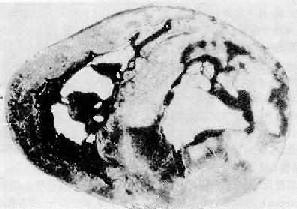

肉眼观,心肌梗死灶形状不规则。一般于梗死6小时后肉眼才能辨认,梗死灶呈苍白色,8~9小时后呈黄色或土黄色,干燥,较硬,失去正常光泽(图8-30)。第4天在梗死灶周边出现明显充血、出血带。2~3周后由于肉芽组织增生而呈红色。5周后梗死灶逐渐被瘢痕组织取代,呈灰白色(陈旧性梗死灶)。

图8-30 心肌梗死

图示心脏横断面由下向上观,图上方为心前壁,左心室前壁和室间隔前部梗死(图中灰白色区)